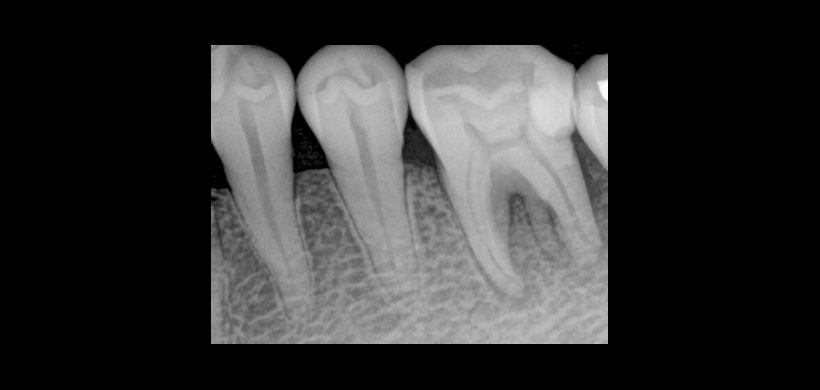

Las pruebas de vitalidad fueron negativas. Debido a eso se optó por adquirir una radiografía periapical revelando una radiolucides alrededor del ápice mesial. (Figura1)